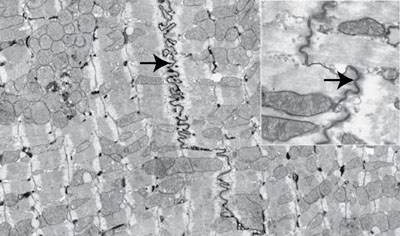

Cardiac Muscle: This photomicrograph of the same tissue taken in phase shows the striations and intercalated disks (arrows) more clearly.